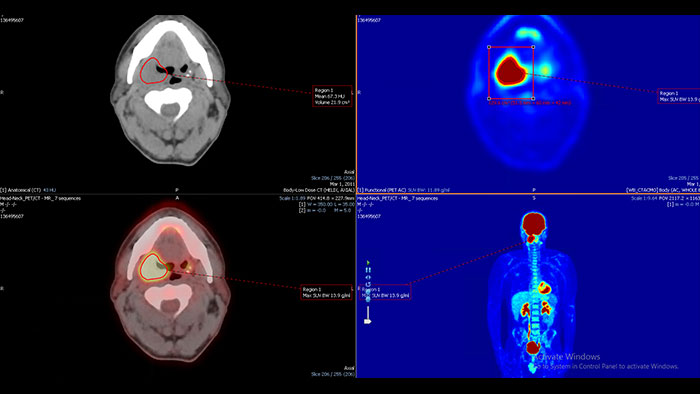

Cedars-Sinai Cardiac Suite 2017

NM Cedars Sinai Cardiac Suite 2017*

Advanced cardiac quantification

Provides comprehensive cardiac quantification tools for gated, perfusion, and blood pool SPECT and quantitative PET. The Cedars-Sinai Cardiac Suite 2017 application provides efficient workflow for study interpretation with integration of perfusion and function.

Benefits

• Automated RV contouring, quantification and analysis.

• Manual perfusion polar map defect editor.

• User customizable viewing layouts.

• Enhanced Phase Analysis algorithm, Smart Launch, color pallet editor.

• QGS, QPS, QBP analysis.

• QPET analysis.